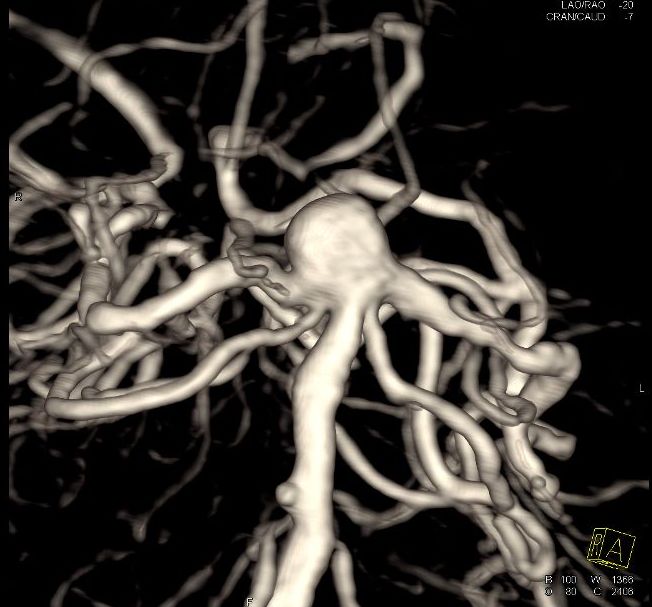

DSA三维成像

从以上病史及检查资料看,病人是入院后常规检查意外发现基底动脉瘤的,没有脑出血症状及不舒服症状。面对这个不定时*弹炸**(动脉瘤)该怎么处理好?

基底动脉末端动脉瘤血管畸形的一种,是血管壁在血流冲击下局部异常变薄所致。这个动脉瘤不是恶性肿瘤,但是一旦动脉瘤破裂,轻者出现头痛头晕,重者昏迷不醒,危及生命!而且你无法预知它什么时候破裂,有时候情绪激动血压升高就可能破裂,有时候用力排便腹压增高也可能引发破裂出血,所以又被称为“不定时*弹炸**”。

对于基底动脉瘤的处理,目前仍有不同的意见(观点):一种是积极去处理(对于出过血的动脉瘤),开颅手术夹闭(手术难度较大,风险高);介入栓塞虽然相对“微创”,但是一旦出现意外破裂,可能会立即危及生命(连上手术开颅急救都来不及)!另一种是如果没有发生过破裂出血的病人,采取保守治疗,控制血压,血糖,维持平和的心态,以减少诱发动脉瘤破裂的诱因,降低动脉瘤出血的机会!

个人认为,对于无症状老年人的基底动脉瘤,还是选择保守治疗,不必要太冒险干预!因为虽然动脉瘤有随时破裂的风险(一旦破裂出血,可能很快危及生命),但是也有一直都稳定不破裂的案例。如果积极干预,则必须有术中可能出现意外,病人马上不行连抢救的机会都没有的心理准备!总之没有绝对的两全其美的事!祝大家健康快乐,诸事顺遂![祈祷][祈祷][祈祷]